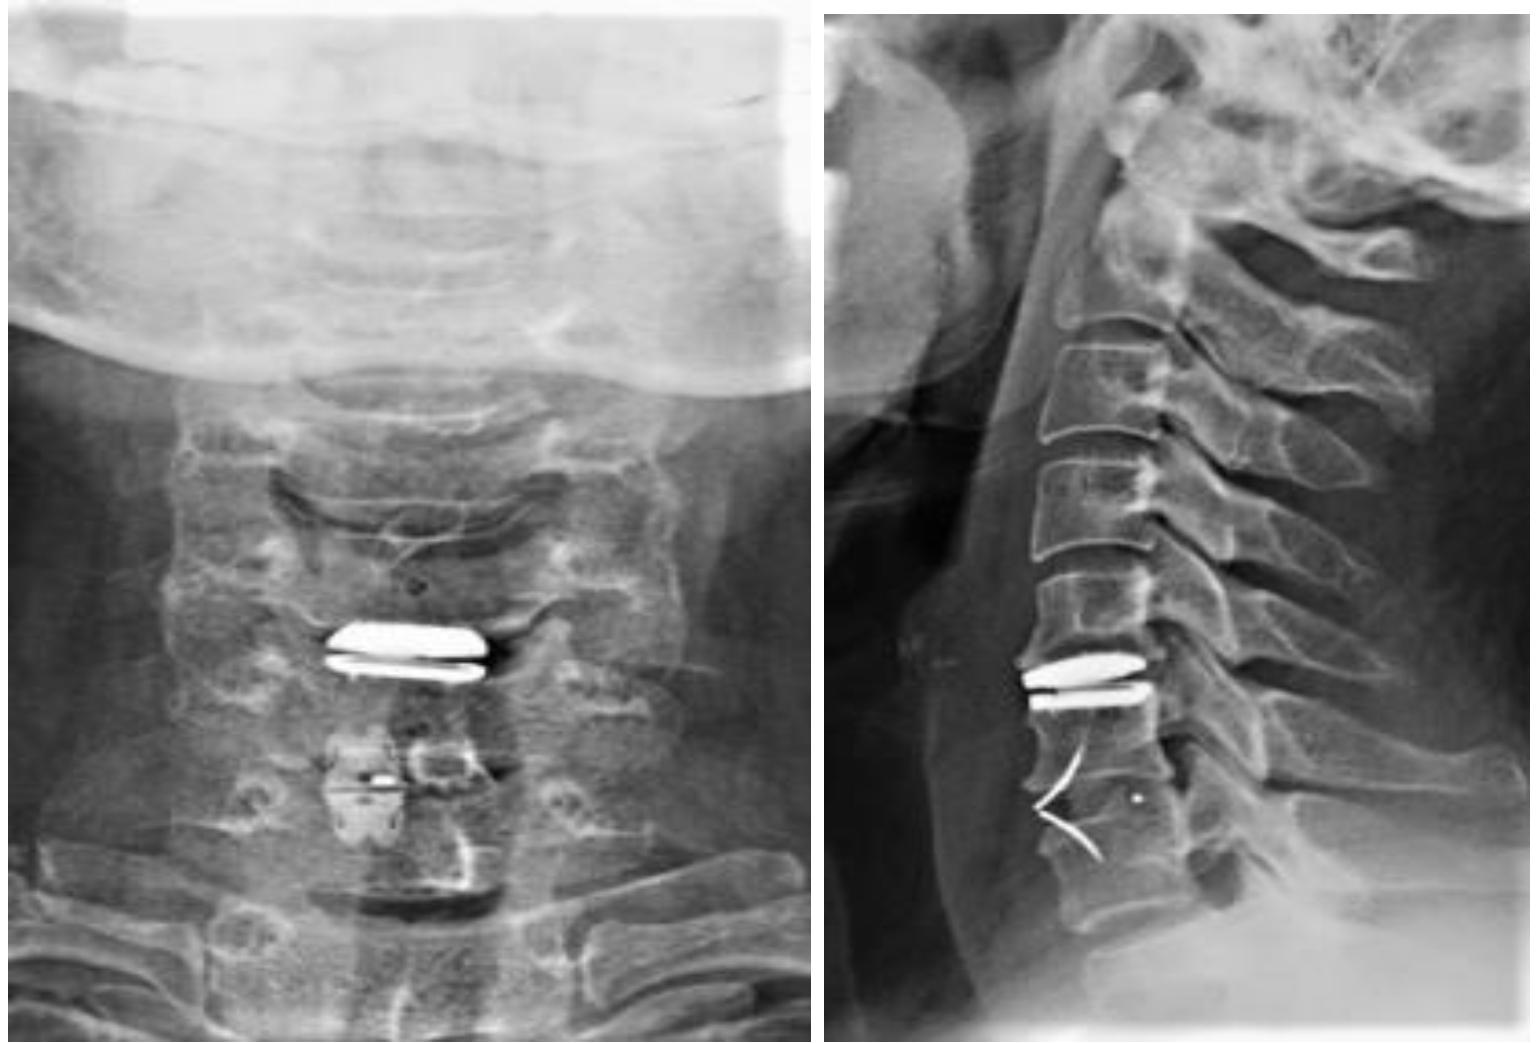

颈椎前路Hybrid术